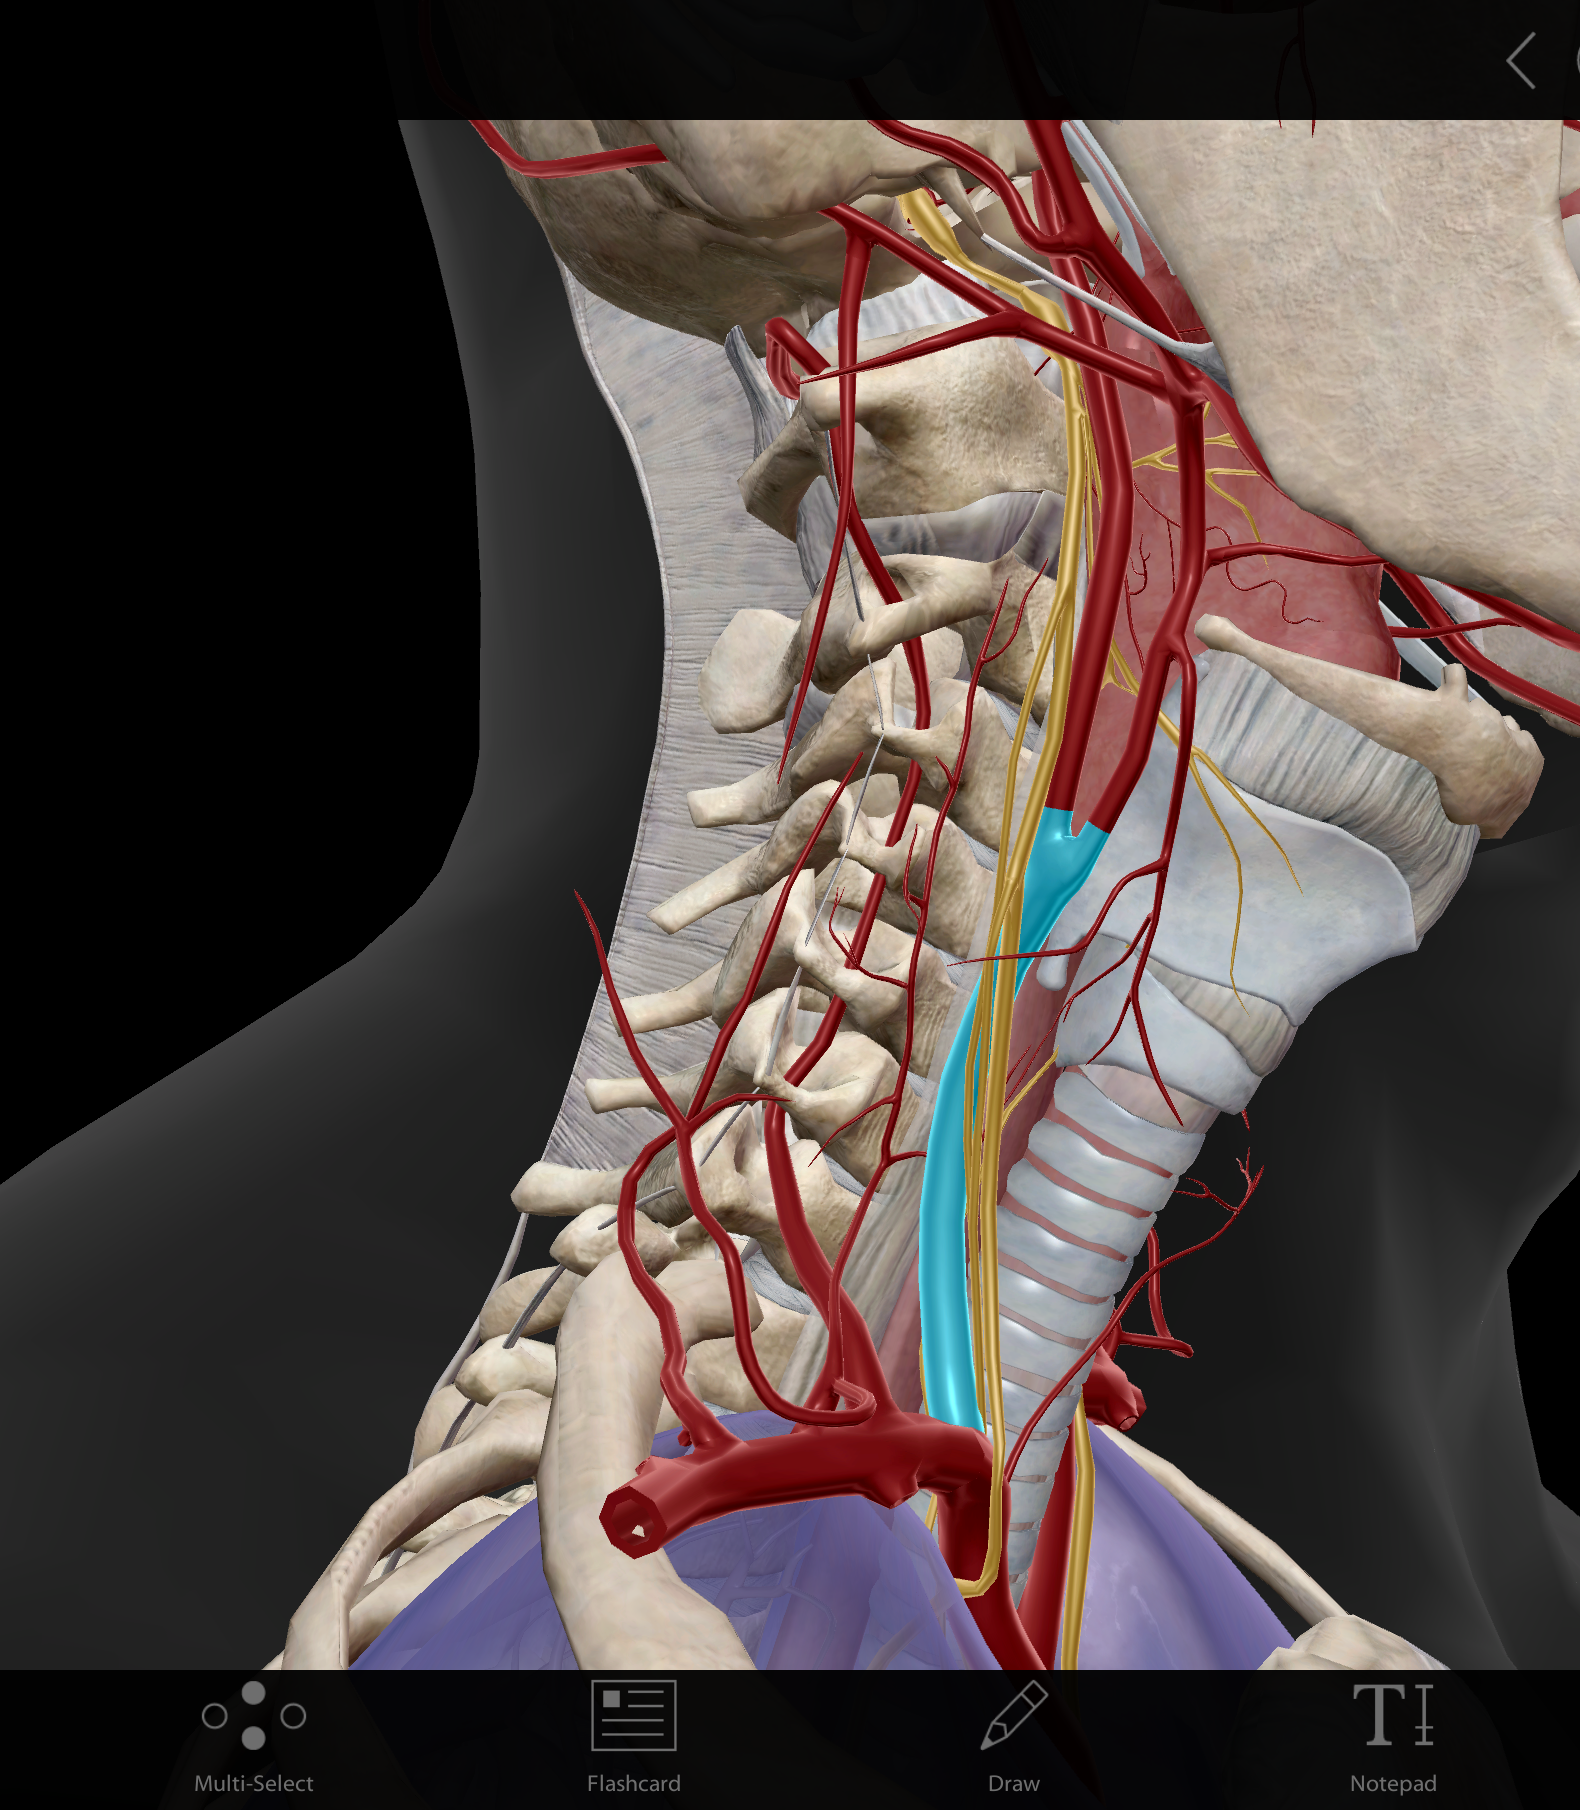

Common carotid a.(L and R)

External carotid a. (L and R)

Internal carotid a. (L and R)